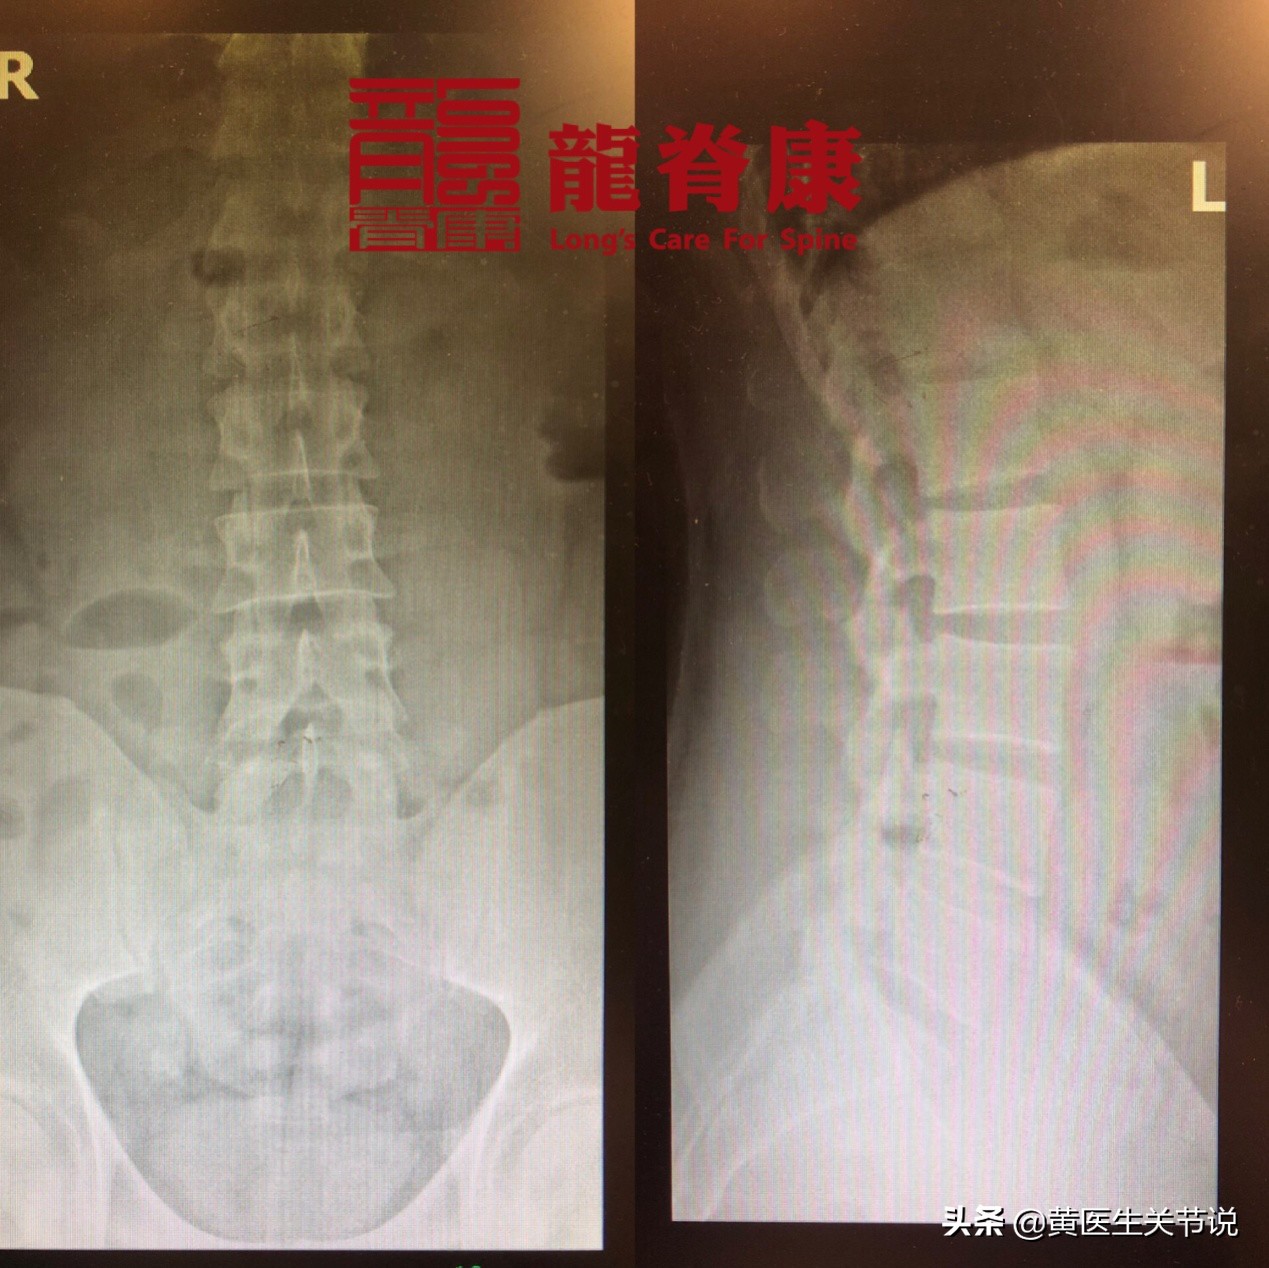

患者首诊X光片

经过三步定位诊断,周先生被确诊为: 腰椎错位引发的急性腰痛。